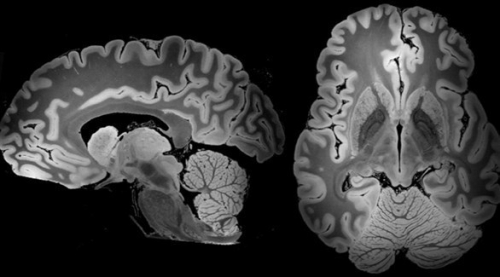

نسبة الحديد بالدماغ تتنبأ بالخرف لدى مرضى باركنسون توصل باحثون إلى طريقة أكثر فاعلية للتنبؤ باحتمال الإصابة بالخرف لدى مرضى الشلل الرعّاش (باركنسون) قب...